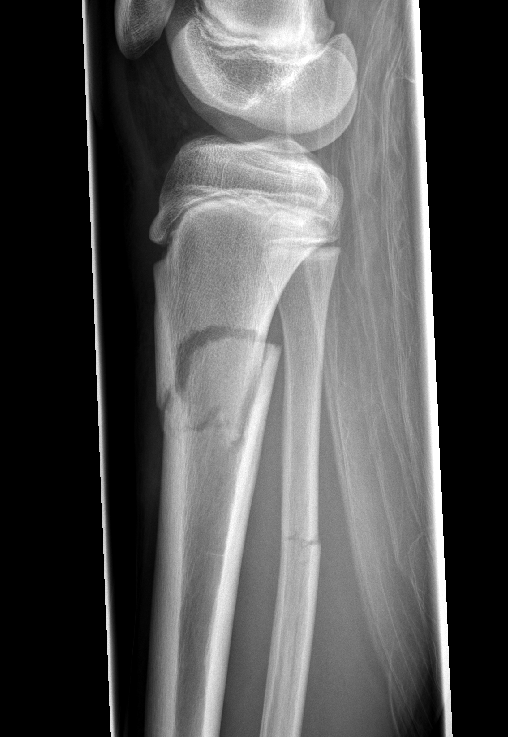

Tell me you’re an ortho resident without actually telling me you’re an ortho resident. #orthotwitter